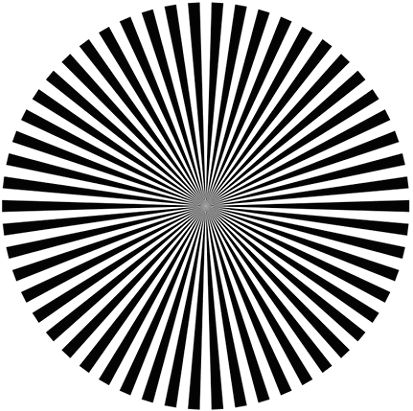

Найбільш інформативний наступний тест: на зображенні, званої Зірка Сіменса, все розходяться лінії абсолютно однакові за кольором і розмірам. При відсутності астигматизму людина бачить такі зміни: чіткі і чорні лінії поступово починають розпливатися, поблизу від центру формується загальний сірий фон, лінії в центрі зображення знову добре видно, але тепер вони здаються білими, а ділянку чіткої видимості променів виглядає, як рівний коло, якщо змінювати відстань від очей до зображення, то при наявності хорошого зору центральне коло буде змінюватися в розмірах.